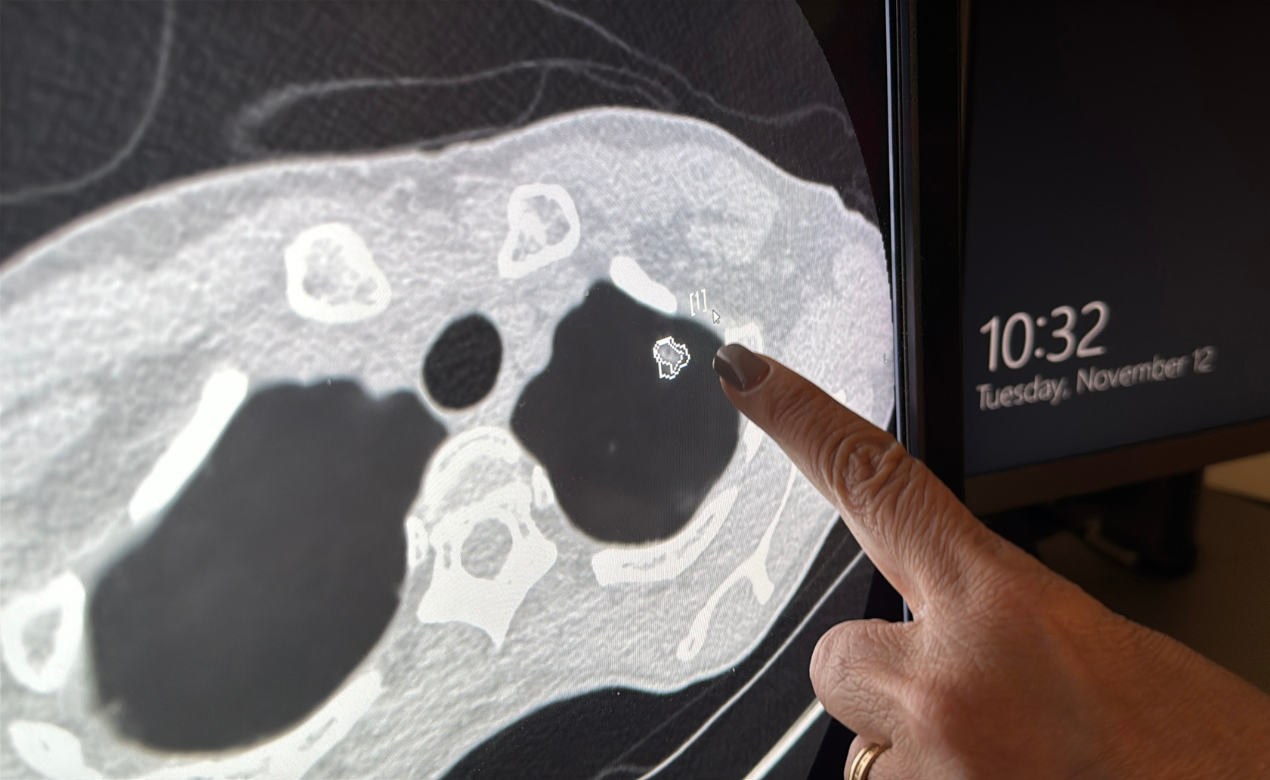

The ClearRead technology narrows down potential problematic nodules by clearing up all normal structures except the nodule from the image, thus removing "visual clutter" and allowing a radiologist like Dr. Kapur to go from focusing on dozens of spots to a handful of spots that truly need attention. The AI software can review scans in a matter of minutes. Despite this, Dr. Kapur calls the AI tool her “second reader” with staff always having the final look.

ClearRead’s unique vessel suppression capability allows radiologists to focus on the areas that matter most, enhancing the conspicuity of lung nodules.

What sets ClearRead apart is its precision in detecting nodules as small as 5 mm. In the past, these small findings could be easily overloofked, buried under a labyrinth of vessels and other normal structures. ClearRead minmizes these obstacles, and every nodule, whether solid, part-solid, or ground-glass, is assessed with improved clarity. This technology even provides automatic measurements for detected nodules, including their type, volume, and dimensions, supporting more accurate assessments.